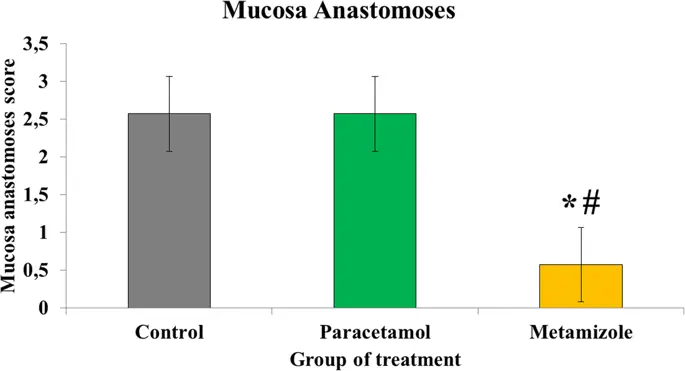

Среднее значение слизистых анастомозов в группе метамизола было ниже (0, 57 ± 0, 5) по сравнению как с парацетамолом (2, 57 ± 0, 5), так и с контрольной (2, 57 ± 0, 5) группами с ап-значением <0, 05. Кроме того, уровень слизистых анастомозов был одинаковым между парацетамолом и контрольной группой (р> 0, 05) ( рис. 4 ).

Оценка анастомоза слизистой оболочки толстой кишки в области анастомоза (*, метамизол против контроля, р <0, 05; #, метамизол против парацетамола, р <0, 05)

Наши результаты также показали, что метамизол ингибирует заживление слизистой оболочки анастомоза, в то время как парацетамол не влияет на процесс. Эти результаты согласуются с данными предыдущих исследований, в которых на прочность суставов анастомоза ободочной кишки крыс не влияло введение как низких, так и высоких доз парацетамола (11). Это может быть связано с центральным эффектом парацетамола, который был более доминирующим, чем периферический эффект в ингибировании синтеза простагландина (11).